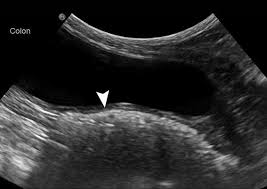

Signs Of Gi Cancer In Dogs / Elements Of Oncology Strategies For Managing Cancer Pain In Dogs Cats - Cancer is a topic that no pet parent wants to think about.. Your veterinarian may recommend the. So now (finally!), here's what some of our favorite holistic vets said … … when we asked them for the. Your vet can ascertain whether the weight loss is related to a cancerous growth or to some other cause and can suggest a course of treatment. Gastrointestinal neoplasia is cancer located anywhere throughout the gastrointestinal (gi) tract, including with gastrointestinal cancer, clinical signs are largely dependent on the location of the cancer diagnosis of gastrointestinal neoplasia in dogs. In humans, chronic disease such as liver disease can lead over time to cancer developing in that organ.

Thanks to the great advancements in veterinary medicine, more and more dogs are surviving, or at least, living much longer than expected. It can originate in the lymph nodes, bone marrow, or organs like the spleen. Types of lung carcinoma in dogs. You can help protect your pet by spotting the danger signs early. Signs of nasal cancer in dogs are abnormal discharge, bleeding, snoring or trouble breathing. And, every cancer is different in how it enters your dog's life. Dogs can get many types of cancer, so the physical signs of cancer can vary according to the specific cancer type. Cancer in dogs may be something you read about, heck you may have had friends whose dogs have dad it. While there are several forms of cancer in dogs, it is important to point out that early diagnosis is often key to a brighter prognosis. Lumps and bumps could be noncancerous, but if they are cancerous then you're more likely to catch it early and fight sooner. Especially as your dog gets older, look out for the symptoms listed here, and never be afraid to ask. Gastrointestinal neoplasia is cancer located anywhere throughout the gastrointestinal (gi) tract, including with gastrointestinal cancer, clinical signs are largely dependent on the location of the cancer diagnosis of gastrointestinal neoplasia in dogs. The warning signs that your dog needs to be evaluated for canine cancer are any sign of painful or altered gait, such as a limp, or positioning to suggest the animal is in pain.

Stomach Cancer In Dogs Bluepearl Pet Hospital from bluepearlvet.com Coats the gastric layer and protects the cells from acids • prostaglandins. Secreted by epithelial cells of stomac and duodenum. Symptoms of canine cancer vary, but any observed lump should be taken seriously. Some lumps are benign, meaning not cancer. Blood or puss, are oozing from your pup, you should relay this information to your vet immediately, as this could be a sign of cancer in the gi tract. Thanks to the great advancements in veterinary medicine, more and more dogs are surviving, or at least, living much longer than expected. Cancer in dogs can be quite common for those aged over 10. Early signs of melanoma in dogs include swollen paws, a.